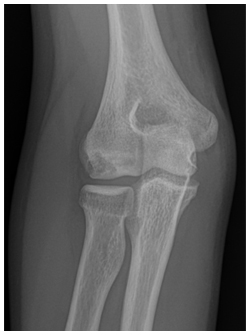

- Radiographs are used to detect the size, location and severity as well as skeletal age of the patient.

- Contralateral X-rays can help determine patients age as the affected side will have premature closure of the capitellum and radial head physes with delayed closure of the medial epicondyle and olecranon physes secondary to valgus stress overload

X-rays demonstrate a large lateral lesion within the capitellum consistent with an OCD lesion. The articular surface appears irregular